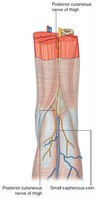

Name structures A to D

(C is the same structure at two separate locations)

A - Popliteal vein

B - Popliteal artery

C - Posterior tibial artery

D - Fibular artery